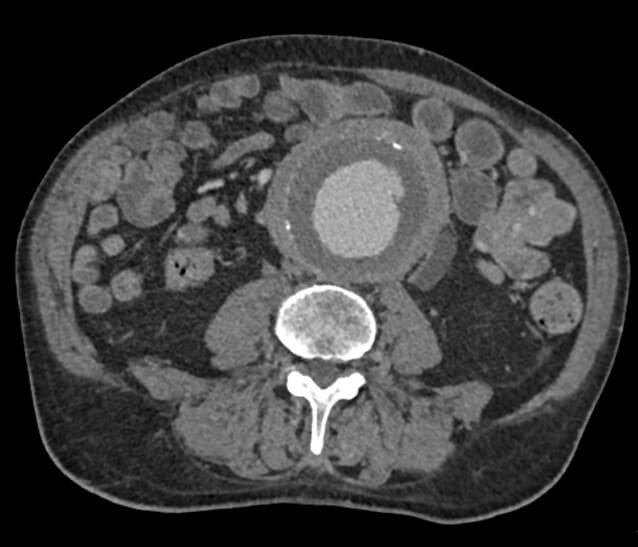

Nel caso di dubbi o approfondimenti diagnostici, può essere eseguita una tomografia computerizzata (TC) con mezzo di contrasto